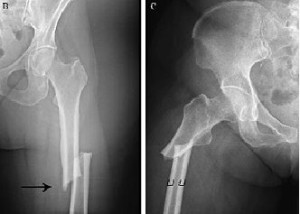

Beneficios y riesgos a largo plazo de los fármacos para prevención de fracturas

Una revisión sistemática muestra que el tratamiento con bifosfonatos luego de 3 a 5 años puede reducir las fracturas vertebrales, pero no previene las no vertebrales y aumenta el riesgo de complicaciones infrecuentes pero severas. Annals of Internal Medicine, 23 de abril de 2019